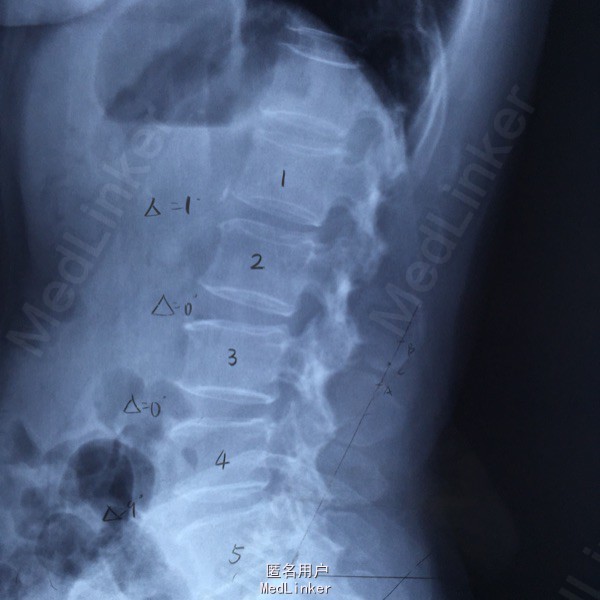

65岁女性,右下肢放射性疼痛2年半,保守治疗效果不佳 2年前曾行C5-6的ACDF术。

L5-S1左侧棘旁压痛(+),右小腿外侧针刺觉稍弱,右侧跟腱反射稍弱。 腰椎CT提示L5-S1间盘突出,偏右侧。 腰椎X线片提示髂嵴偏高,L5横突肥大。

L5-S1椎间盘突出 C5-6 ACDF术后 拟行椎间孔镜手术